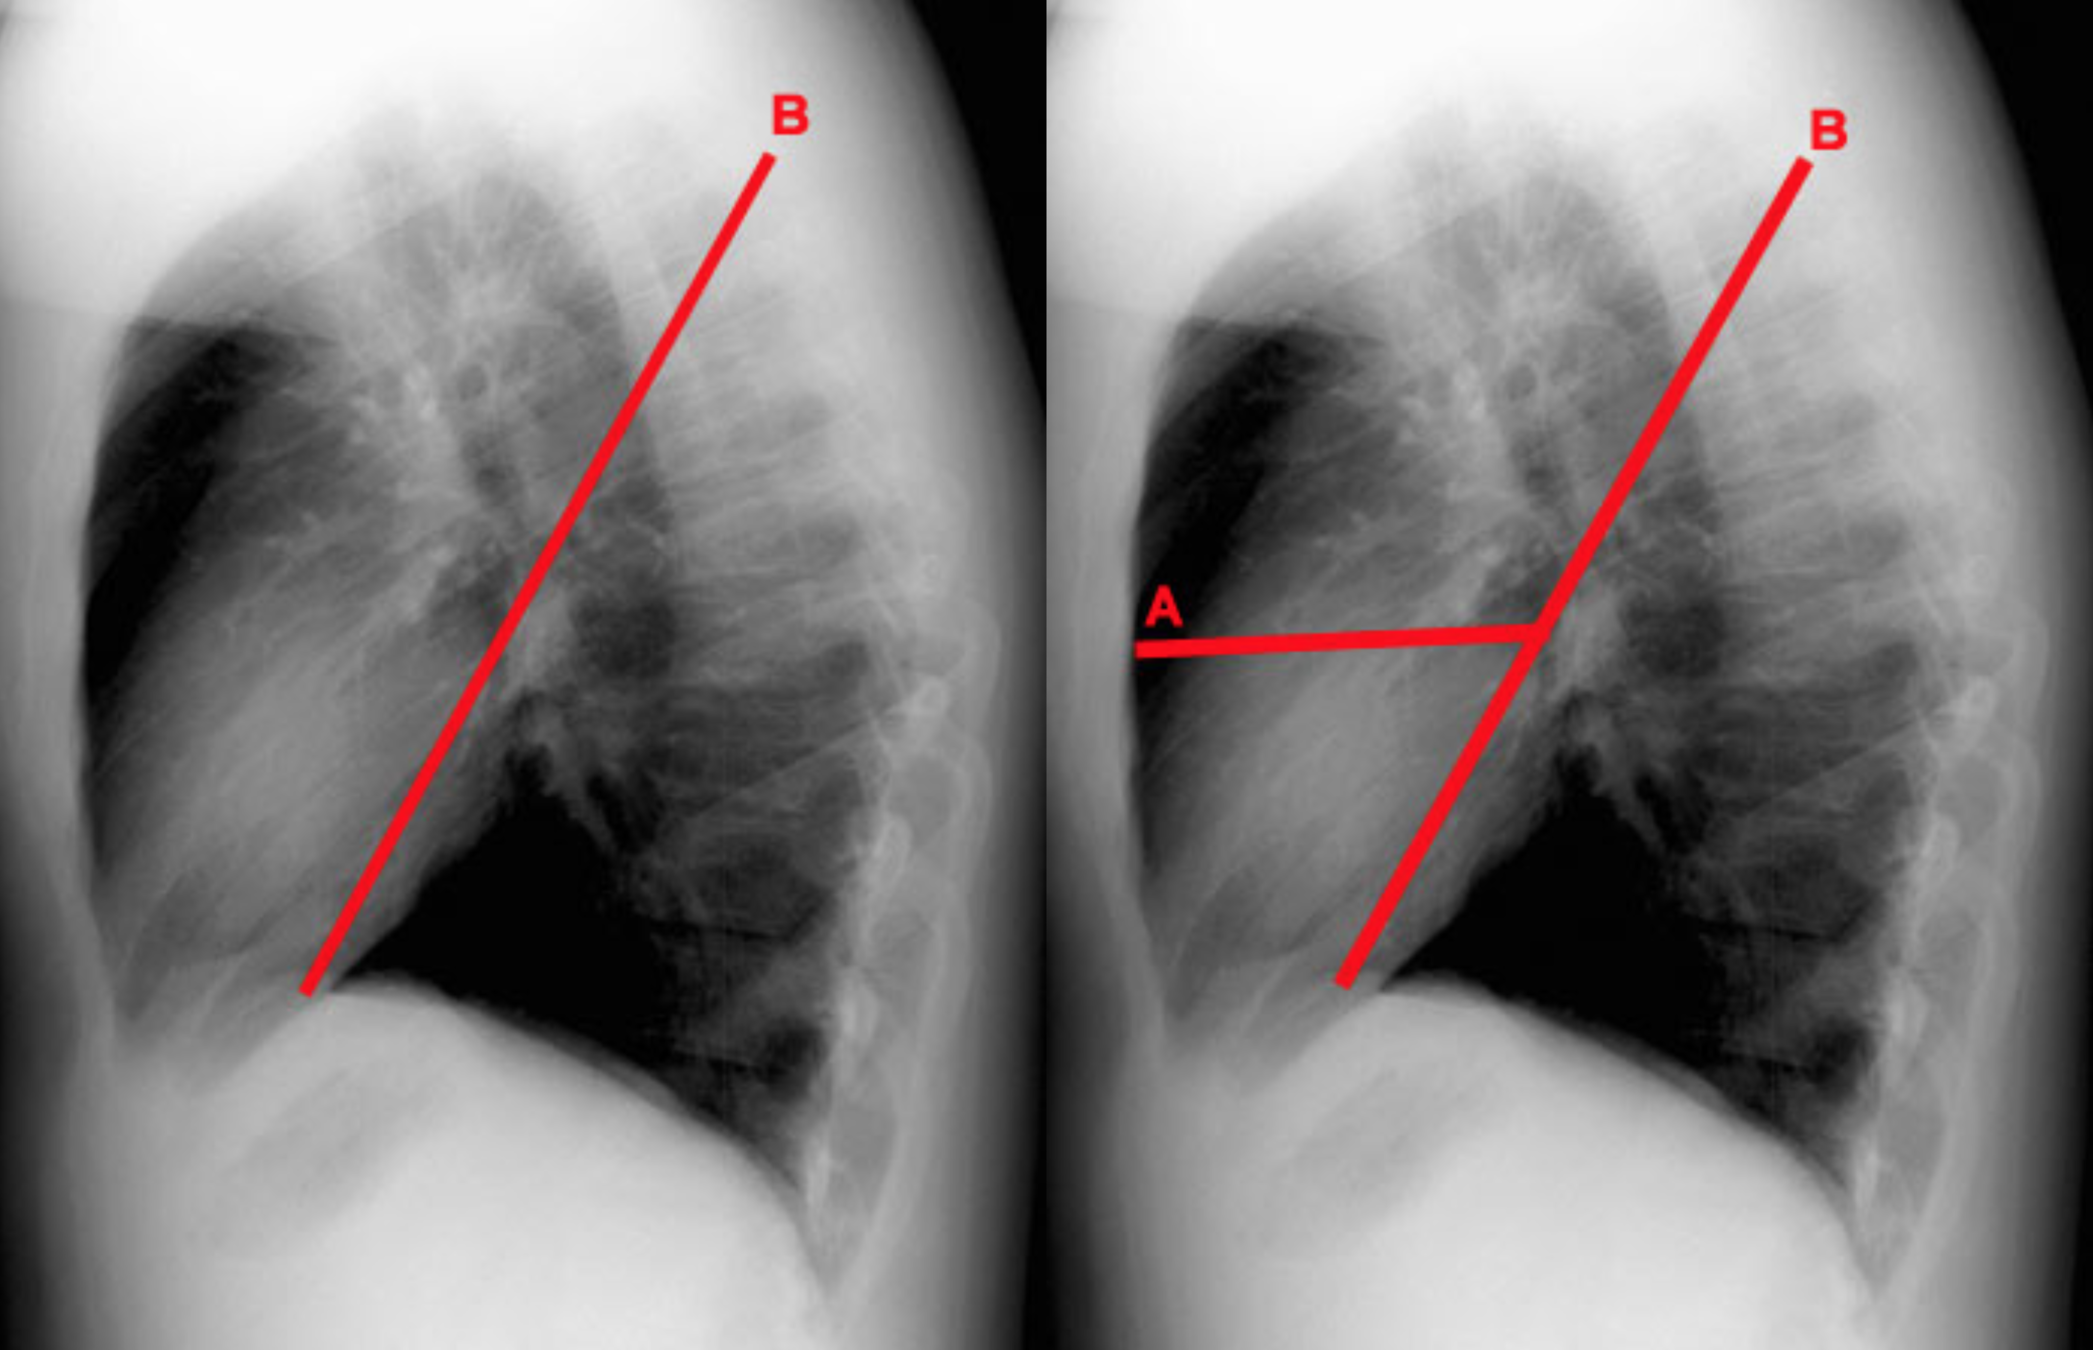

A: Minor Fissure

B: Major Fissure